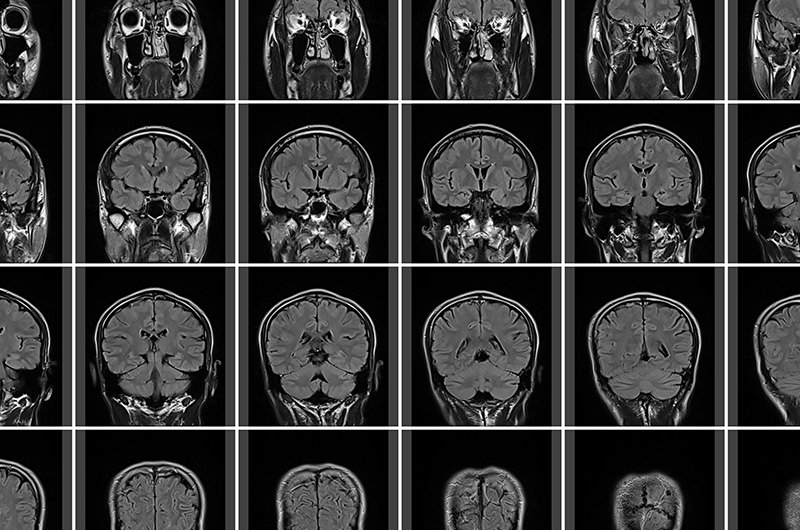

身体の断面図を撮影する検査

MRI検査とは、強力な磁力と電波を使って身体の断面図を撮影する検査方法です。

レントゲンやCTのように放射線を使いませんので被ばくの恐れはなく、造影剤を使わなくても血管が診ることができ、おおよそ20分程度横になっていただくだけで、鮮明な画像を得ることができます。

脳神経外科・脳神経内科の領域では、脳卒中などの脳血管障害、脳腫瘍、頭部外傷、認知症などの発見・診断を目的に行われます。

MRI検査でわかること

現在の異常、そして過去の異常を発見

MRI検査で、現時点で発生している脳梗塞や脳出血の発見・診断が可能なほか、くも膜下出血の原因となる脳動脈瘤の有無、また過去に発生していた無症候性脳梗塞(隠れ脳梗塞)、古い脳梗塞のあとや脳出血のあとなども発見することができます。

MRI検査

強力な磁力と電波を使って身体の断面図を撮影し、無症候性脳梗塞(隠れ脳梗塞)、脳出血、脳萎縮などを確認します。